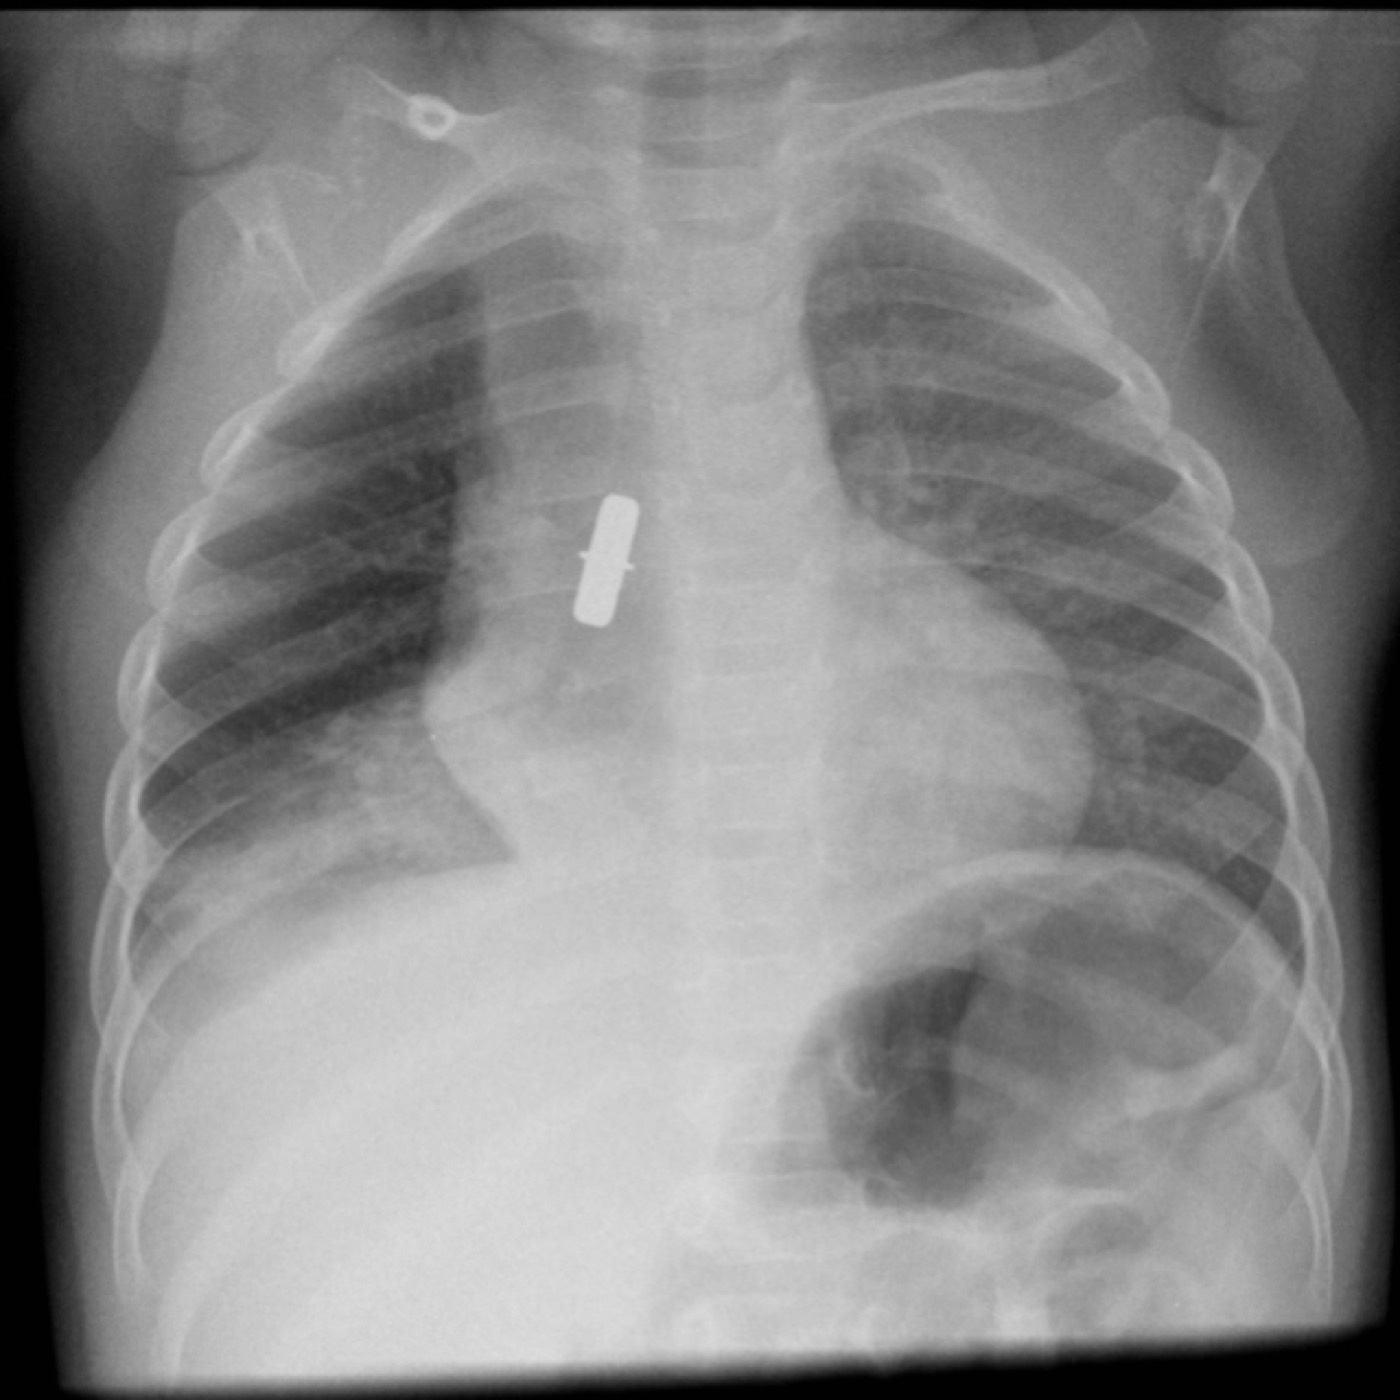

Contributors: Travis Barlock MD, Jeffrey Olson MS4 Feel free to use the cases below for your own practice. All of the scenarios are completely made up and designed to hit several teaching points. Case 1 25 M, presents to the ED with chest pain. Stabbing, started a few hours ago, substernal. Thinks it is GERD. After 2-3 minutes, pain worsens and radiates to the back. VS: BP 125/50 (Right arm 190/110). HR 120. RR of 18. Sat 98% on RA. Additional VS: Temp of 37.2, height of 6'5", BMI of 18. PMH: None, doesn't see a doctor. Meds: None FH: Weird heart thing (Mitral Valve Prolapse), weird lung thing (spontaneous pneumothorax), tall family members with long fingers and toes Physical Exam: Cards: Diastolic decrescendo at the RUSB, diminished S2. UE pulses are asymmetric, LE pulses are asymmetric, carotid pulses are asymmetric, BP is asymmetric MSK: Knees, elbows, and wrists are hypermobile. Imaging: CXR #1 normal, #2 widened mediastinum (no read yet but shows widened mediastinum), POCUS shows small effusion CTA/MRA doesn't come back until after the case. ECG: Sinus Tach Labs: NT-proBNP 500 pg/mL D-Dimer: 7000 ng/L CBC: Hemoglobin: 13.5 g/dL, WBC: 20,000/µL, Platelets: 250,000/µL Chem 7: Na 138, K, 5.7, Cl 102, Bicarb 17, BUN 45, Creatinine: 3.5 mg/dL, Glucose: 180 LFTs: Albumin 2.4, Total protein 5.5, ALP: 140, AST: 3500, ALT: 2800, TBili: 3.2, DirectBili: 2.4, Ca: 7.8 LDH: 2200 PT: 20.5, INR: 2.2, Fibrinogen: 170 5th gen High-Sensitivity Troponin: <3 Lactate: 7 mmol/L VBG: pH 7.22, paCO2 28, bicarb 15 Notes: Can have patient crash somewhere in middle and show 2nd xray Case 2: A 67-year-old female is brought to the ED by her daughter due to progressive weakness, confusion, and fatigue that have worsened over the past week. Unable to get out of bed and has become increasingly lethargic. Also having some nausea, constipation. The daughter denies any preceding illness, recent trauma, or travel. Does not know her meds but will head home to get them after talking with you. VS: BP 88/55 mmHg, HR 110, RR 20, O2 Sat 98% on room air. Additional VS: Temp 36.8°C. PMH: Hypertension, osteoarthritis, and depression. Physical exam: General: Thin, somnolent but arousable. HENT: Dry mucous membranes Neuro: Confused, A&Ox1 (self), hyporeflexia Labs (Includes many that would not return in the ED in case you want to take this case forward to the floor) CBC: WBC 9,500, Hb 16.5, Hct: 50%, Platelets 220,000 Chem7: Na 129, K 2.1, Cl 95, HCO3 34, Creatinine 1.6, BUN 40, Glucose 115 LFTs: normal Magnesium: 1.1 Calcium: 10.8 mg/dL (corrects to 12.8) iCal: 3.2 Phosphate: 2.3 mg/dL Albumin: 2 BUN:Cr ratio: 25 VBG: pH: 7.49, PaCO2 45, HCO3: 34 Lactate: 2.8 Serum Osmolality: 276 mOsm/kg (Osmolal gap of 2) Urine Osmolality: 550 mOsm/kg Urine Sodium (UNa): 10 mEq/L (low). Urine Potassium (UK): 25 mEq/L (elevated). Urine Chloride (UCl): 12 mEq/L (low). Urine Magnesium (UMg): 20 (Elevated). Urine Calcium (UCa): 50 in 24 hrs (Low) 100 cc of urine with foley FeNa Plasma renin activity: 15 mg/mL/hr (elevated), Aldosterone: 25 ng/dL (Elevated), ADH: Elevated, Diuretic screen: Positive for thiazides PTH: 8 (low), HsTrop: 32, Cortisol and ACTH: Normal. EKG: Hypokalemia features CXR: Normal Renal US: shows stones Improves with fluids Note: Can have daughter return with med list at some point including HCTZ, ibuprofen, and sertraline Case 3: Patient Presentation EMS Report: A 27-year-old male involved in a high-speed motorcycle collision is brought to the emergency department by EMS. The patient was found unconscious at the scene with evidence of severe thoracic and extremity trauma. He was intubated en route for airway protection due to altered mental status (GCS 7). VS: HR 130, BP 90/60, RR: bagging at 12 bpm, satting 88% on 100% FiO2 Primary Survey Airway: Endotracheal tube in place. Breathing: Decreased breath sounds on the left side with visible chest asymmetry and paradoxical chest wall movement. Circulation: Mottled extremities noted, with significant deformity of the right thigh. Pulses are diminished in the right leg Disability: GCS remains 7 (E1 V2 M4). Pupils equal and reactive. Exposure: Full-body examination reveals an open fracture of the right femur, multiple abrasions, and bruising over the chest wall. Vent alarms Peak Inspiratory Pressure (PIP) 40 cm H₂O (elevated) Plateau Pressure (Pplat) 35 cm H₂O (elevated) EtCO₂ (End-Tidal CO₂) 55 mmHg High-Pressure Alarm Triggering frequently Glucose 120 CBC: Hgb 8.9, Hct 27, WBC 14.2, platelets 220,000 VBG: pH 7.28, pCO2 33, bicarb 18, lactate 4.5 CXR with tension pneumothorax Patient improves after chest tube, pigtail catheter, or needle decompression. Ready to be transferred upstairs and O2 starts tanking again Vent alarms- second episode Peak Inspiratory Pressure (PIP) 35 cm H₂O (elevated) Plateau Pressure (Pplat) 30 cm H₂O (elevated) EtCO₂ (End-Tidal CO₂) 20 mmHg HR: 140, satting 84%, temp 38.5, ABG: pH 7.32, pCO₂ 30 mmHg, pO₂ 60 mmHg on 100% FiO₂, HCO₃⁻ 18 mmol/L (hypoxemia and metabolic acidosis). D-dimer: Elevated Thrombocytopenia: Platelets 90,000/µL. US shows blown right ventricle ECG shows new RBBB CT PE: Ground glass opacities, consolidation, centrilobular nodules, septal thickening, and fat-attenuating lesions. Note: Management is largely supportive care so once the diagnosis is made, end the case. References Carroll MF, Schade DS. A practical approach to hypercalcemia. Am Fam Physician. 2003 May 1;67(9):1959-66. PMID: 12751658. Coelho SG, Almeida AG. Marfan syndrome revisited: From genetics to the clinic. Rev Port Cardiol (Engl Ed). 2020 Apr;39(4):215-226. English, Portuguese. doi: 10.1016/j.repc.2019.09.008. Epub 2020 May 18. PMID: 32439107. Palmer BF. Metabolic complications associated with use of diuretics. Semin Nephrol. 2011 Nov;31(6):542-52. doi: 10.1016/j.semnephrol.2011.09.009. PMID: 22099511. Reed MJ. Diagnosis and management of acute aortic dissection in the emergency department. Br J Hosp Med (Lond). 2024 Apr 30;85(4):1-9. doi: 10.12968/hmed.2023.0366. PMID: 38708978. Roberts DJ, Leigh-Smith S, Faris PD, Blackmore C, Ball CG, Robertson HL, Dixon E, James MT, Kirkpatrick AW, Kortbeek JB, Stelfox HT. Clinical Presentation of Patients With Tension Pneumothorax: A Systematic Review. Ann Surg. 2015 Jun;261(6):1068-78. doi: 10.1097/SLA.0000000000001073. PMID: 25563887. Rothberg DL, Makarewich CA. Fat Embolism and Fat Embolism Syndrome. J Am Acad Orthop Surg. 2019 Apr 15;27(8):e346-e355. doi: 10.5435/JAAOS-D-17-00571. PMID: 30958807. Produced by Jeffrey Olson, MS4 Special thanks to Evan Fisch MD Get your tickets to Tox Talks Event, Sept 11, 2025: https://emergencymedicalminute.org/events-2/ Donate: https://emergencymedicalminute.org/donate/